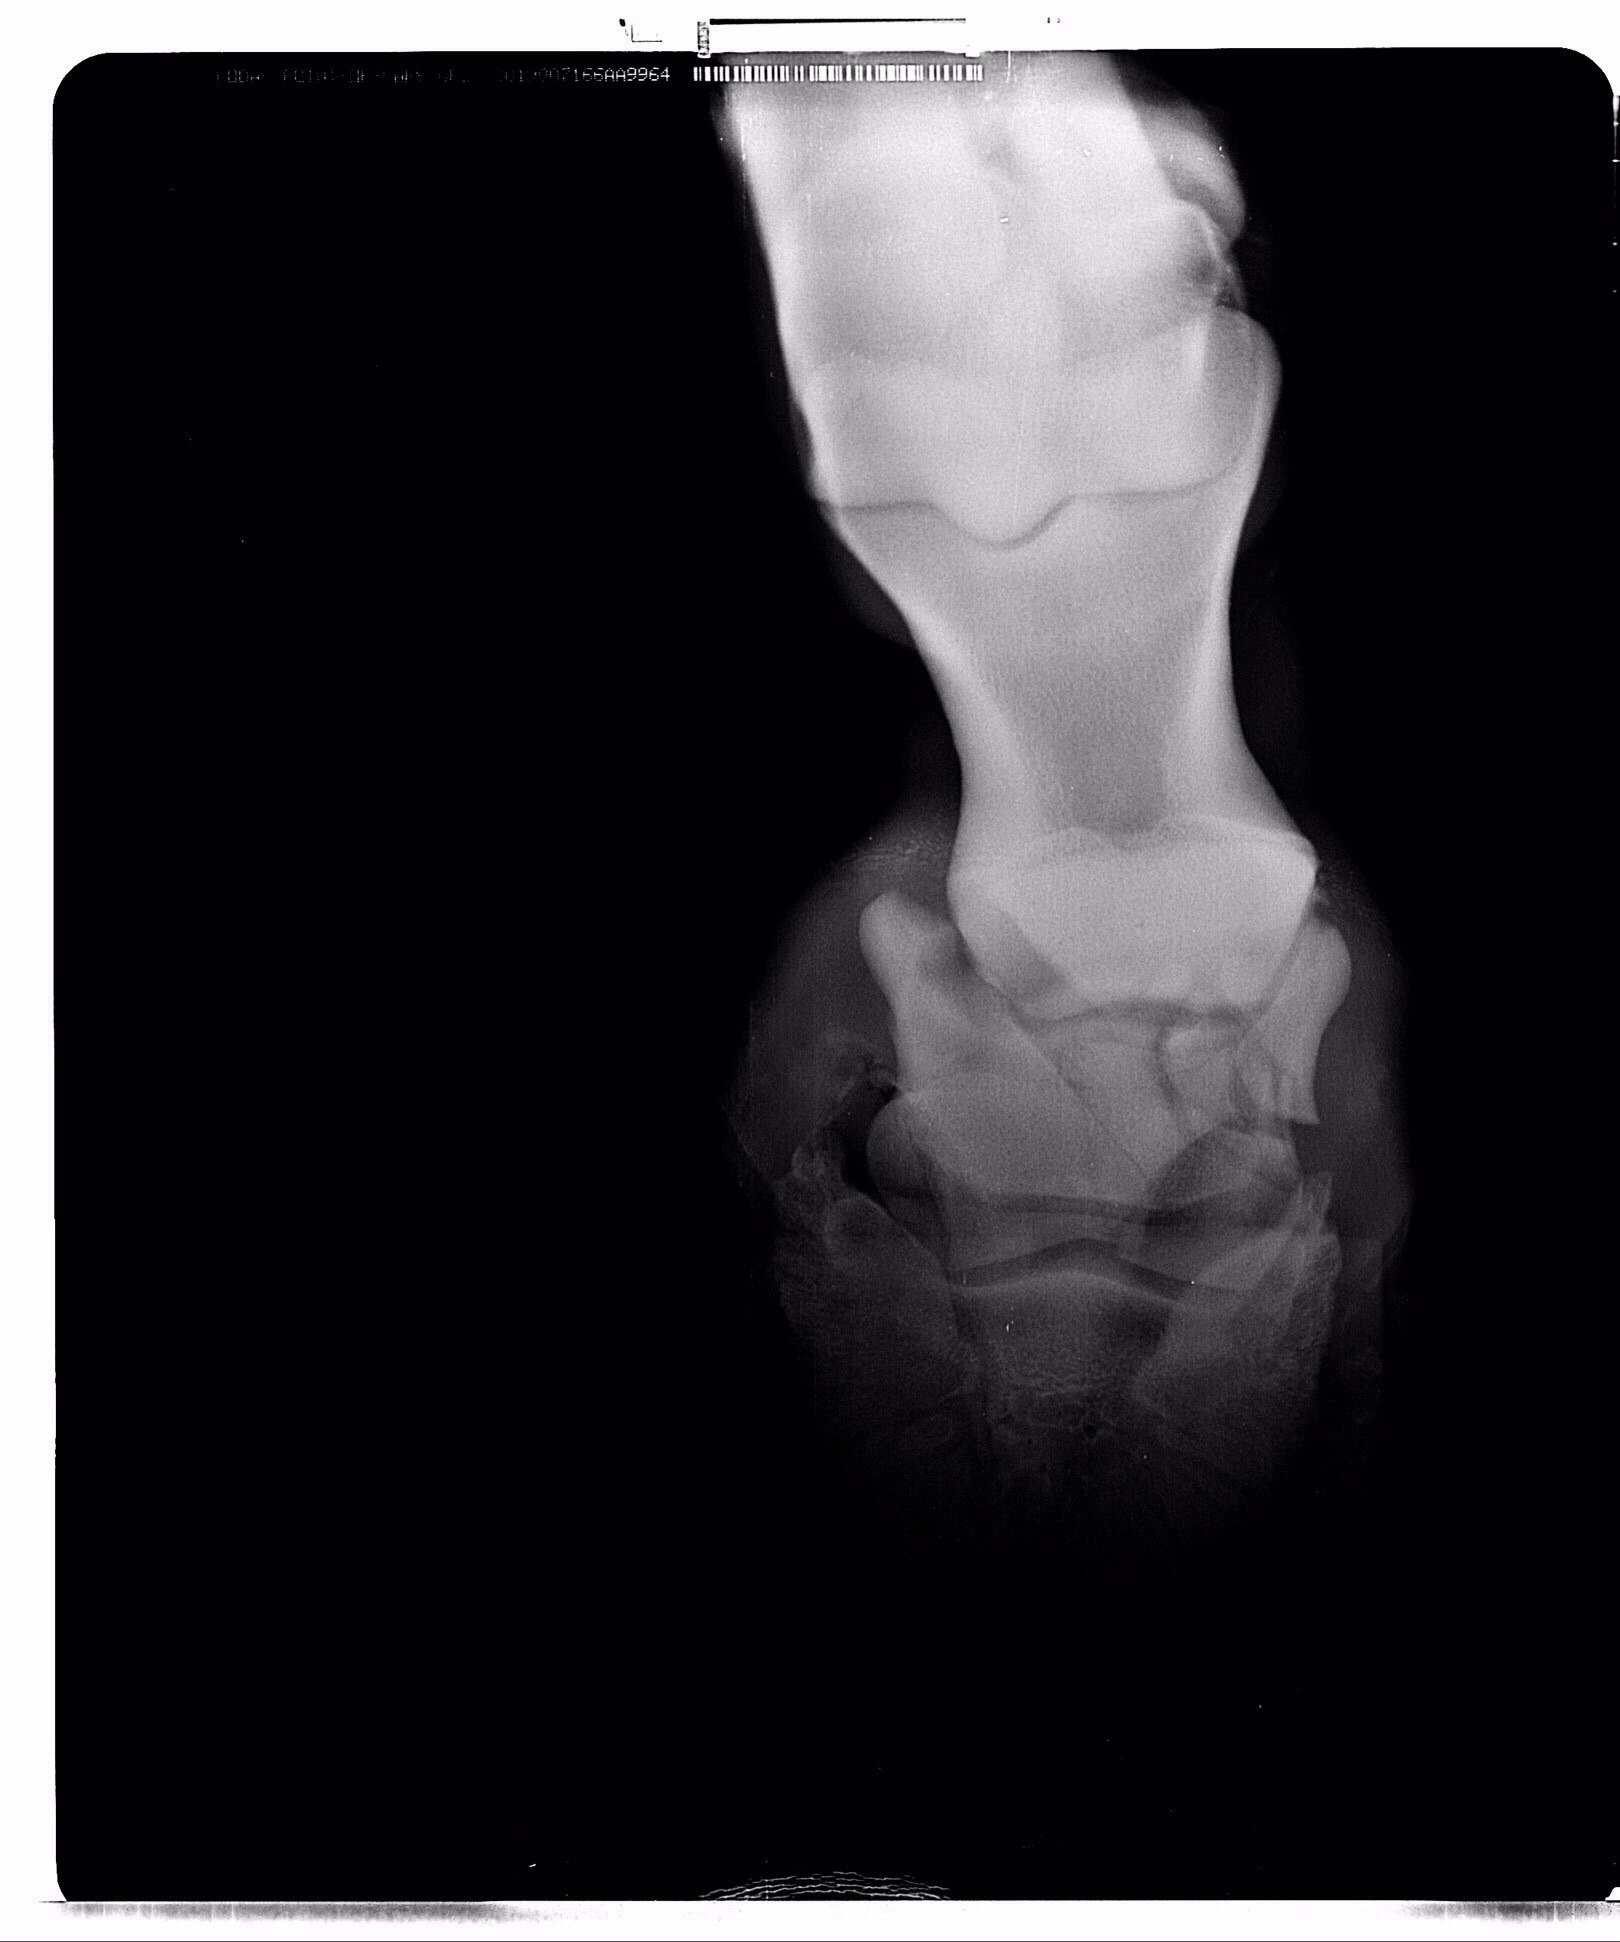

Жеребец. Винтовой перелом путовой кости на ЛЗ почти по всей её длине, внизу перелома смещение 5 отломков.

Брался НВ - остеосинтез на пластины и штифты. перегипсовка каждые определенные периоды. Наложение гипса при таких переломах отличается на передней ноге получен перелом или задней. На задней сложнее. Нужен наркоз каждый раз.

Стоял с гипсом 2,5 месяца, постоянные рентгены, жрал кучу всего. Гипс он как-то так продавил пяткой или что еще сделал, но получился, как костыль, на который он мог опираться и как-то даже перемещался по деннику. Сразу научился ложиться, вытягивая ногу и также вставать. Он сразу хотел жить и делал всё от него зависящее. Вот в этот период у него было отличное дыхание, что вообще никто не может объяснить.

Делающие рентгены ветеринары (Отрада, Эквимедика) говорили, что его случай противоречит медицинской практике и опыту. И что это магия

На месте сращения отломков образовалась шишка, предупредили, что это жабка (вроде так) и она может расти дальше.